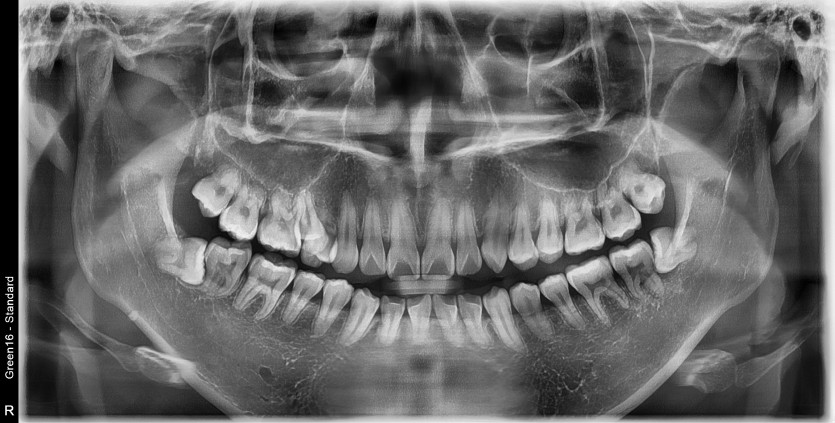

#28,38 사랑니 발치

구강 외과 전문의가 당일 발치했습니다.